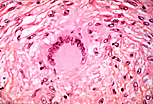

光镜下,巨细胞的识别依据是其体积巨大,且共同胞质内含有多个细胞核。 |

当细胞核在胞质内随机分布时,该巨细胞称为米勒细胞(Müller)。 |

当细胞核呈环形或马蹄形排列时,该巨细胞称为朗汉斯细胞(Langhans)。 |